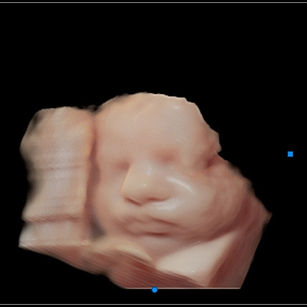

Skin: Becoming smoother as fat builds up underneath; baby is starting to look plumper and less wrinkly.

Muscles: Strengthening—movements are more coordinated and powerful.

Eyes: Baby can respond to light, open and close their eyes, and even start practicing blinking.